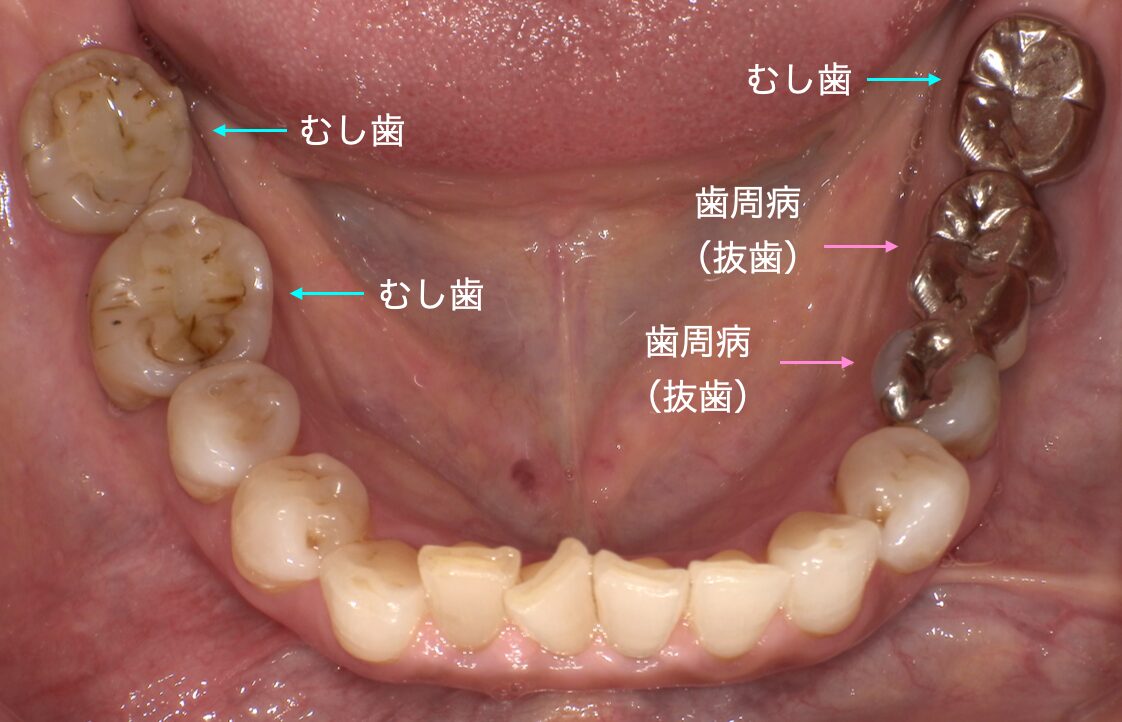

CASE 症例紹介

当院では、歯周病治療やインプラント治療、セラミック治療、審美治療など、様々な治療オプションを用いて、お口の中全体を管理しています。

院長が施術してきた症例をご確認のうえ、お気軽にご相談・ご来院ください。